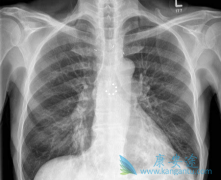

化疗是小细胞肺癌的基本治疗方法。同步放化疗可以改善局限期(LD,即所有病灶都可以包含在一个放射野)患者的生存。具有更广泛病变的患者被归类为广泛期(ED),只能接受化疗。最近在Anticancer Research杂志上发表的一项随机II期临床试验的研究结果在有 ...